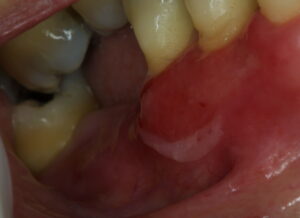

The mouth is the most frequent site of involvement in patients with cicatricial pemphigoid; it is often the first (and only) site affected. Lesions often involve the gingiva, buccal mucosa, and palate ; other sites such as the alveolar ridge, tongue, and lips are also susceptible. A frequent oral manifestation is desquamative gingivitis. Other lesions may present as tense blisters that rupture easily or as mucosal erosions that form as a consequence of epithelial fragility. Lesions in the mouth may result in a delicate white pattern of reticulated scarring. In severe disease, adhesions may develop between the buccal mucosa and the alveolar process, around the uvula and tonsillar fossae, and between the tongue and the floor of the mouth. Gingival involvement can result in tissue loss and dental complications (e.g., caries, periodontal ligament damage, and loss of bone mass and teeth).